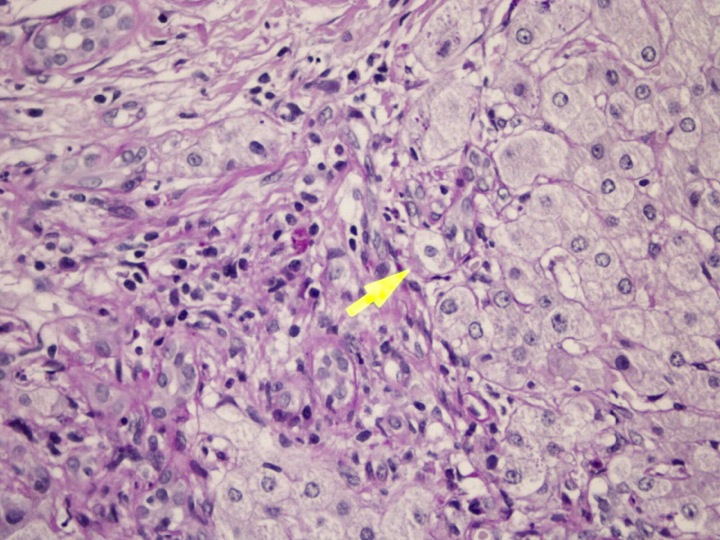

En la biopsia realizada a la paciente, se observa una arquitectura hepática alterada por la presencia de proliferación de tejido conjuntivo e infiltrado inflamatorio que rompe la lámina limitante. Proliferación de conductillos que en ocasiones están dañados. Focos inflamatorios en el parénquima y hepatocitos balonizados. En conclusión, hepatitis crónica activa, grado 3/6 de fibrosis y 9/18 de actividad, compatible con etiología autoinmune.